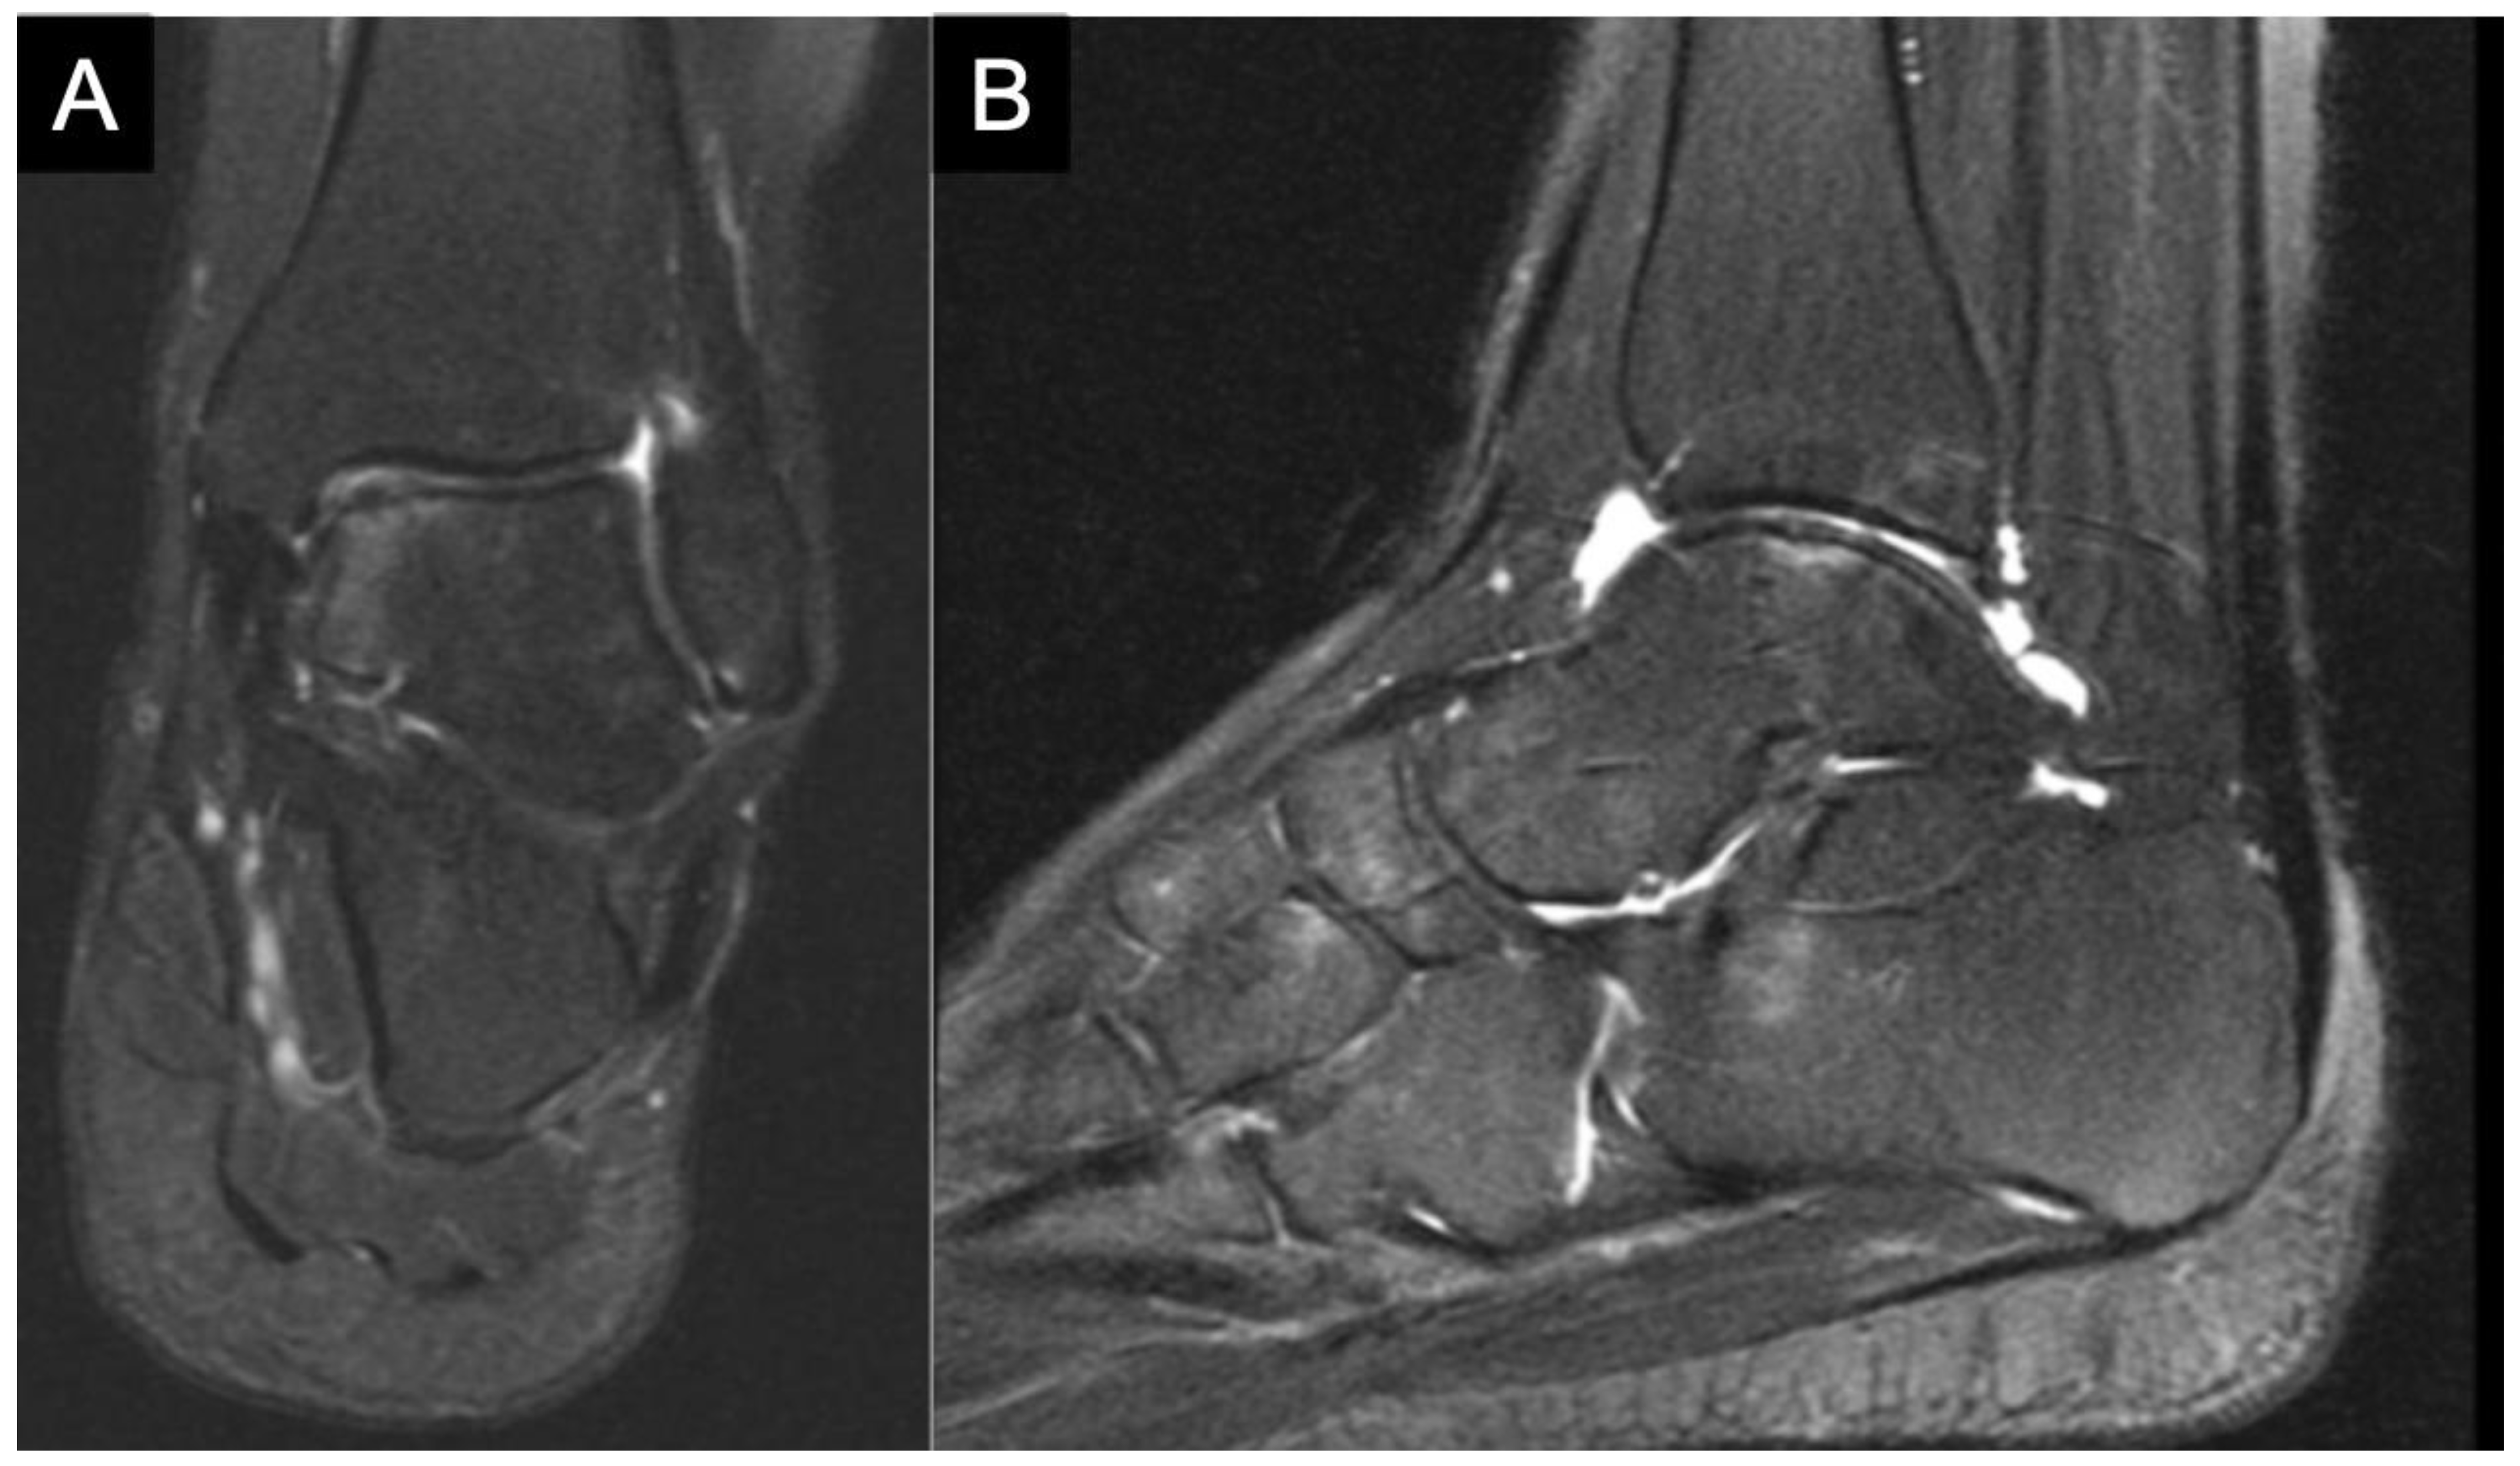

3. Diagnostics